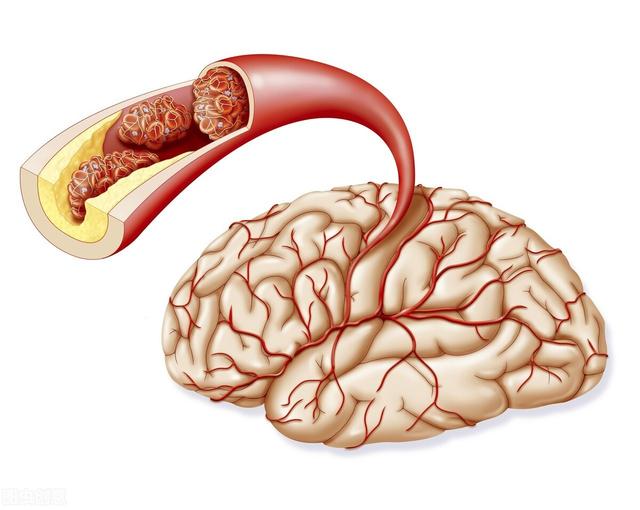

Notre cerveau gère presque toutes les fonctions de notre corps et est connu comme le commandant du corps. Le cerveau dépend du sang pour transporter l'oxygène et les nutriments dont il a besoin. Lorsque les vaisseaux sanguins sont bloqués pour diverses raisons, le cerveau est incapable d'obtenir de l'oxygène et des nutriments et meurt, entraînant la perte de fonctions de notre corps, ce qui est appelé infarctus cérébral. Les fonctions des différentes parties du cerveau étant différentes, les patients auront des séquelles plus ou moins importantes selon la localisation et l'étendue de la nécrose. Certaines personnes peuvent n'avoir qu'un léger vertige et découvrir qu'elles ont subi un infarctus cérébral lorsqu'elles se rendent à l'hôpital pour un examen (la plupart des patients atteints d'infarctus cérébral lacunaire sont découverts au cours de l'examen). Certains patients garderont des séquelles telles que l'hémiplégie, l'immobilité, la cécité, le retard mental, voire la mort.

L'infarctus cérébral est en fait un trouble de l'irrigation sanguine des vaisseaux sanguins du cerveau, qui se traduit par une irrigation sanguine insuffisante du cerveau, ce qui déclenche l'ischémie et l'hypoxie et aggrave encore la nécrose ischémique ou le ramollissement du tissu cérébral. L'infarctus cérébral représente la majorité des accidents vasculaires cérébraux dans la pratique clinique, et les types d'accidents vasculaires cérébraux les plus courants sont les suivantsThrombose cérébrale, infarctus lacunaire et embolie cérébraleetc.

L'infarctus cérébral est divisé en plusieurs types en fonction des différentes causes de l'infarctus : la rupture de la plaque causée par l'athérosclérose, formant un thrombus qui bloque les vaisseaux sanguins cérébraux, forme un infarctus cérébral ; l'embolie formée dans la région du cœur en raison d'une fibrillation auriculaire, d'un flutter auriculaire, d'une insuffisance cardiaque, d'une maladie valvulaire cardiaque, etc., qui pénètre dans les vaisseaux sanguins cérébraux avec le flux sanguin pour bloquer les vaisseaux sanguins cérébraux, forme également un infarctus cérébral ; l'occlusion des petits vaisseaux sanguins des artères cérébrales en raison d'un durcissement et de lésions, etc. forme également un infarctus cérébral, et ces infarctus cérébraux se produisent lentement en termes de pathogenèse. Ces infarctus cérébraux, bien qu'ils soient lents à se produire, mais lorsque les vaisseaux sanguins cérébraux sont soudainement bloqués, en particulier les vaisseaux sanguins importants responsables de l'approvisionnement en sang du cerveau, l'infarctus cérébral se produit d'un seul coup et il n'y a pas trop de précurseurs pour que nous puissions y faire face. L'infarctus cérébral se produit directement lorsqu'il entraîne directement dans le corps une hémiplégie, une aphasie, une ataxie, qui peuvent être accompagnées de maux de tête sévères, de nausées, de vomissements et d'autres symptômes, et l'état peut rapidement évoluer vers un infarctus cérébral. Par conséquent, pour prévenir l'infarctus cérébral, nous devrions toujours contrôler activement le risque à partir de la pathogenèse, et l'idée de se fier aux précurseurs ou aux symptômes précoces pour juger du risque d'infarctus cérébral est très difficile à mettre en œuvre pour prévenir le risque et intervenir à l'avance.

L'infarctus cérébral est également appeléInfarctus cérébral ou accident vasculaire cérébral ischémique (AVC ischémique cérébral)Ce terme désigne la nécrose ou le ramollissement du tissu cérébral dû à un manque d'apport sanguin au cerveau, qui se produit à la suite d'une ischémie ou d'une hypoxie.